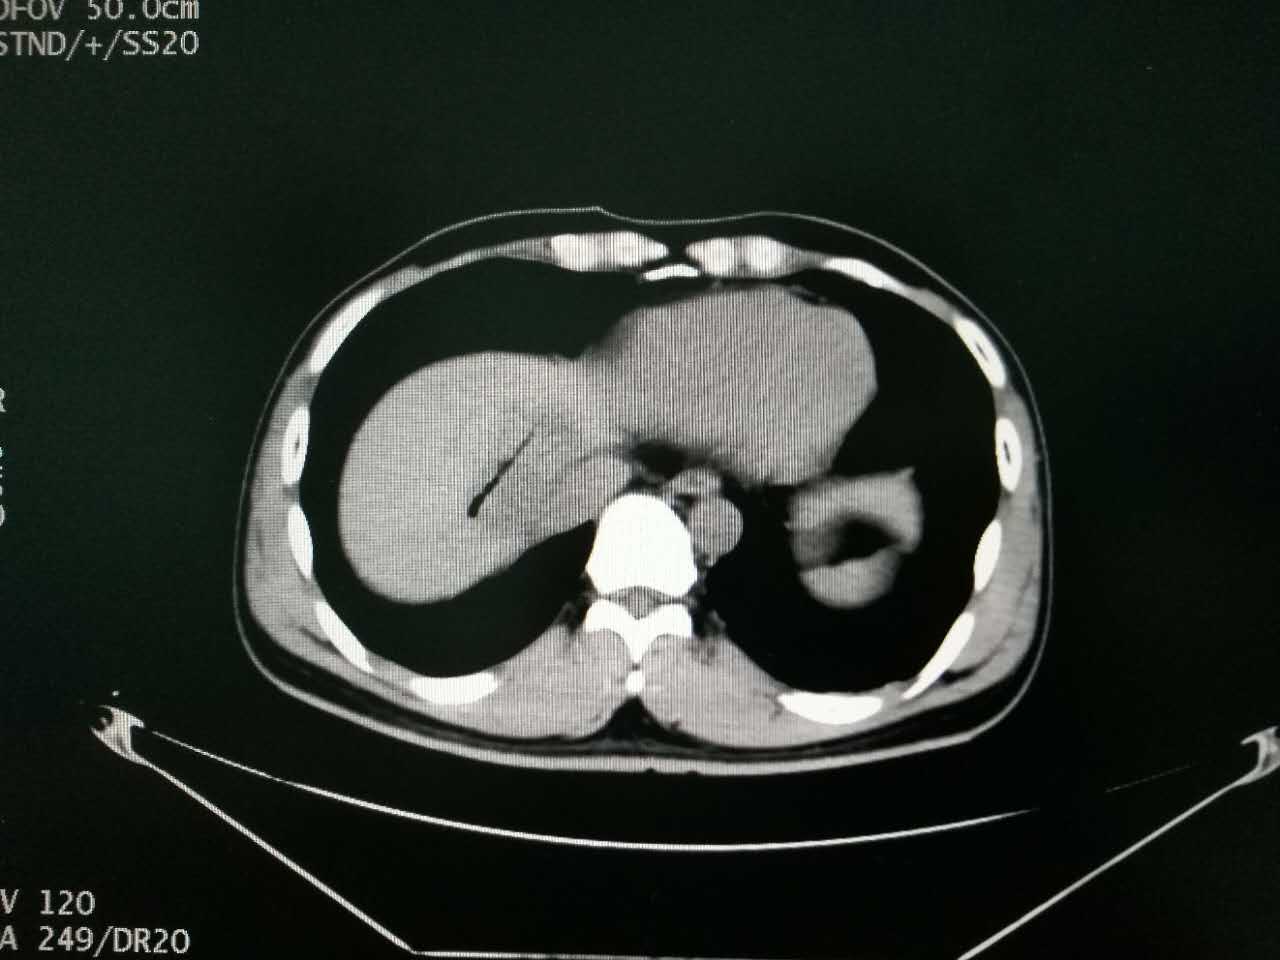

更让人心痛的是,经检查,他的肝脏肿瘤位置非常特殊:不仅位于膈脚下腔静脉旁,而且距离心脏只有1.5cm,不宜再行传统外科手术。常规肿瘤消融术又不足以彻底消灭肿瘤,那该怎么办呢?

经过广州现代医院MDT(多学科专家协作诊疗团队)会诊讨论,决定给患者进行不可逆电穿孔消融(纳米刀)手术

▲患者肝脏肿瘤距离心脏1.5cm,位于膈脚下腔静脉旁